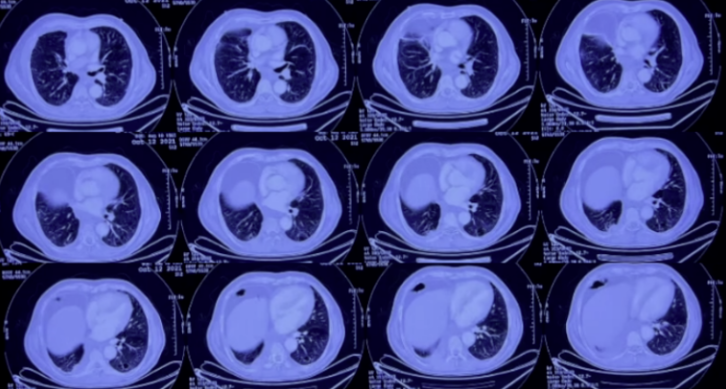

2022年1月28日复查胸部CT:双肺感染仍然较重,虽未完全吸收,但较前有好转(图11)。

图11 复查胸部CT(2022-01-28)

2022年2月18日胸部CT:双肺病灶较前进一步吸收,右下肺脓肿尚未完全吸收(图12)。

图12 复查胸部CT(2022-02-18)